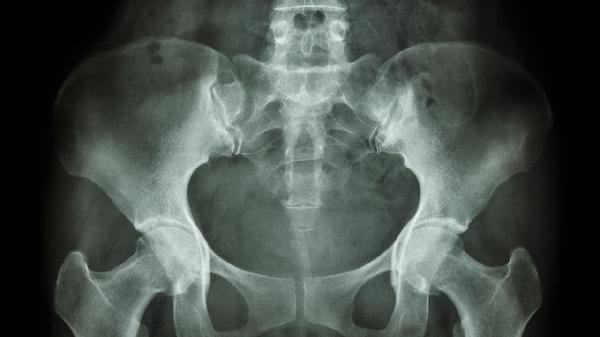

骨盆肿瘤并非都是恶性的,可能由遗传因素、环境刺激、慢性炎症、良性骨病变或恶性肿瘤转移引起。

骨囊肿、骨纤维异常增殖症等良性病变常见于骨盆。无症状者可暂不处理,体积增大压迫神经时需行病灶刮除+骨水泥填充,或采用射频消融等微创治疗。

原发性骨肉瘤或转移癌如乳腺癌、前列腺癌转移需立即干预。综合治疗包括新辅助化疗甲氨蝶呤+阿霉素、根治性手术半骨盆切除术及靶向治疗安罗替尼。